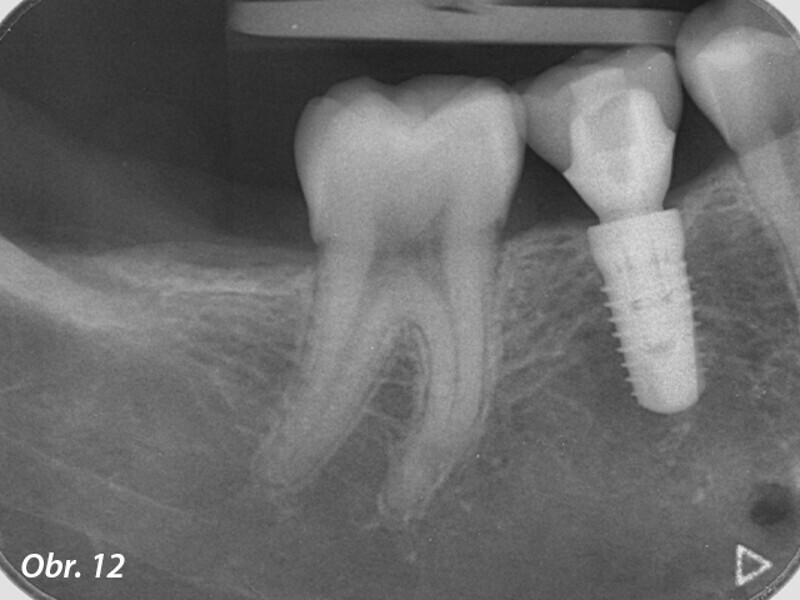

Řízená implantologie za použití řešení Planmeca all-in-one